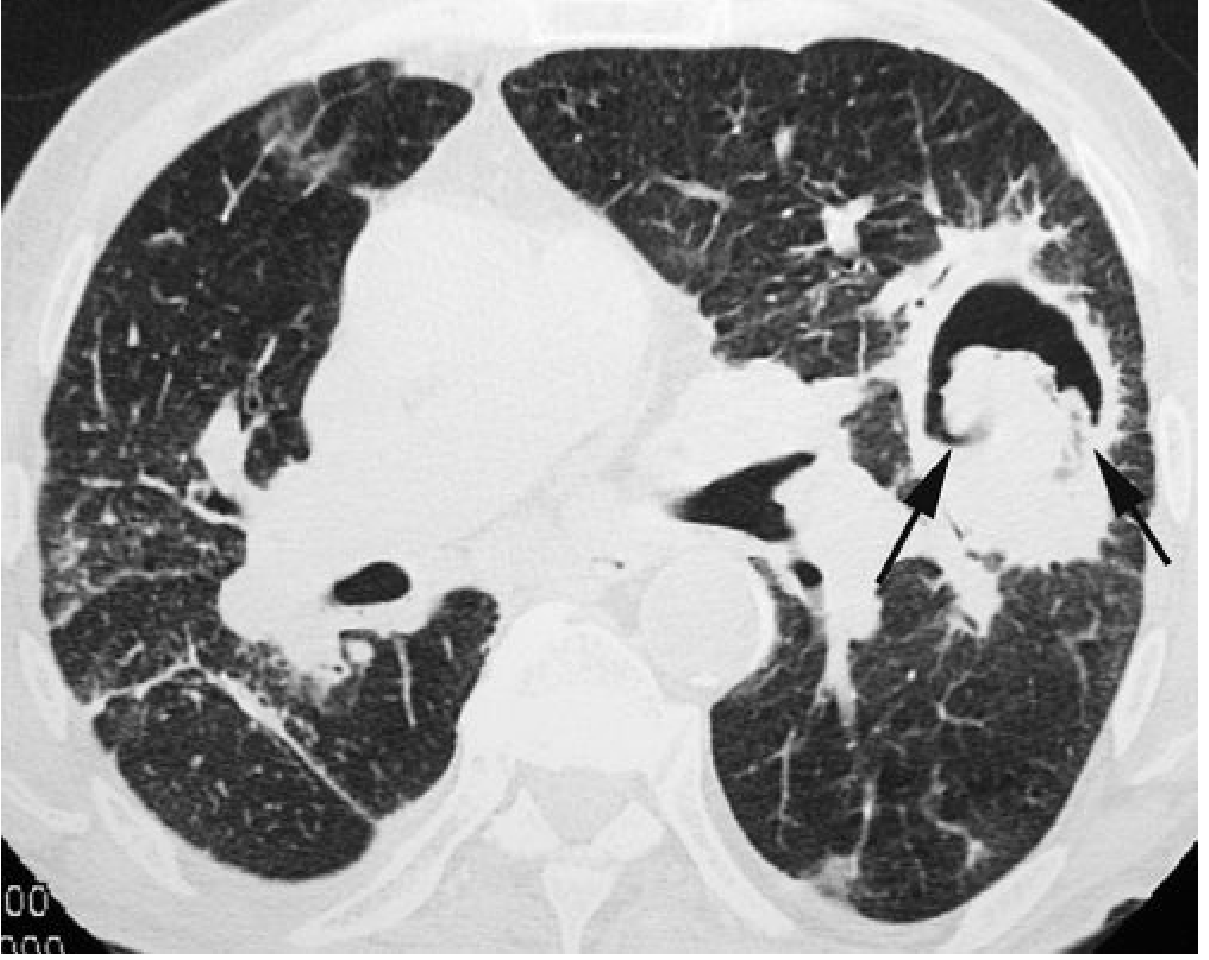

Imaging: A rounded soft-tissue mass sitting within a cavity, separated from the wall by a crescent of air — the Monod sign (or air crescent sign in this context). The ball moves with position changes on decubitus films.

CT: left upper lobe cavity with fungus ball (arrows) — Monod sign